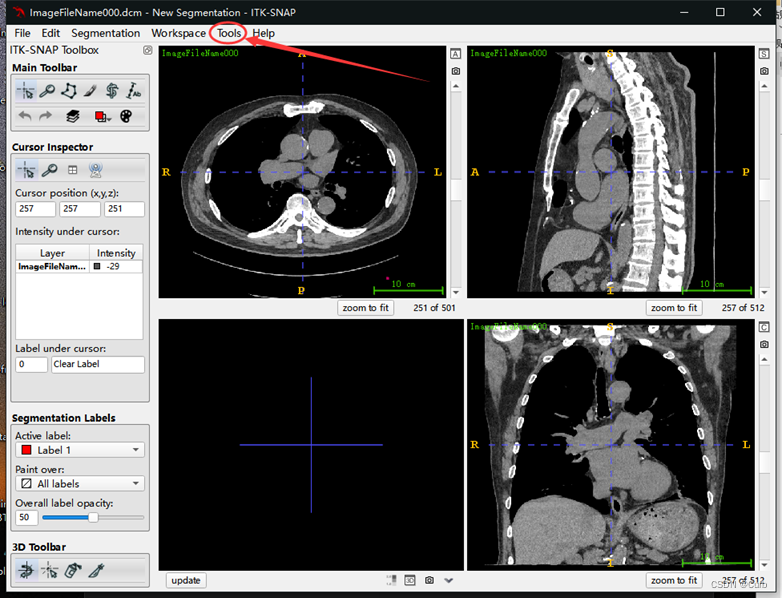

打开过后的效果如下

3 窗宽窗位调节

先点击Tools,再点击Color Map Editor,出现以下画面,通过修改Level和Window来调节窗位和窗宽。这里根据以上参考,设置窗位为40,设置窗宽为400(可以发现心脏各部分的轮廓很清晰)。